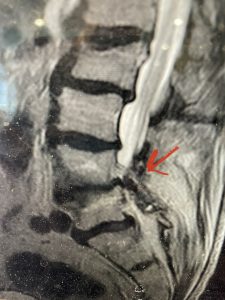

(Fig 2) Sagittal T2-weighted lumbar MRI demonstrating (arrow) tight lateral recess stenosis

This 57 year-old male had a long history of low back pain and left lower extremity pain and numbness. The patient had failed conservative treatment of physical therapy and epidurals. MRI revealed tight left L2-3 and L3-4 lateral recess stenosis as well as significant right L4-5 facet arthropathy and right lateral recess stenosis as well as a grade 1 L4-5 spondylolisthesis

It was felt that the patient should undergo surgical decompression and fusion at L4-5 given his spondylolisthesis. Post operatively he had an uneventful course and he had relief of his leg pain.